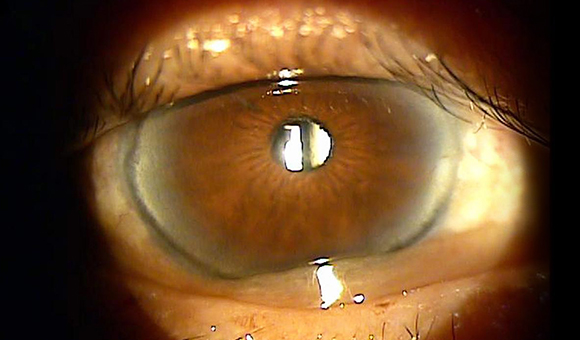

눈물흘림의 원인이 되는 질환, 결막낭성형술

내안각부위에 발생할 경우 누점을 막아 누액배출을 방해하여 눈물흘림증, 눈가짓무름을 유발합니다.

결막낭성형술의 수술목적

수술 전

수술 후